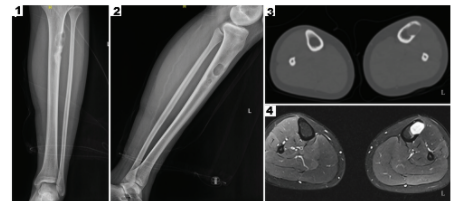

في عام 2022 تم نشر حالة عن استخدام الطباعة الحيويَّة ثلاثيَّة الابعاد لأول مرة من أجل تخليق عظام نشطة لإصلاح العيوب العظمية في مجلة (International Journal of Bioprinting) [12]، إذ راجعت مريضة عمرها 16 عاماً بآلام متقطعة في عضلة الساق اليسرى استمرت لستة أشهر. ثم تطورت الآلام في الجزء العلوي من ساقها اليسرى بعد ممارسة الرياضة متبوعة بنوبات متقطعة من الألم. كانت الكتلة الورميَّة ملموسة في الجزء العلوي من الساق بحجم (1×1 سم) بحدود غير واضحة وحركة ضعيفة وألم خفيف عند الضغط. وقد أظهرت صورة الاشعة السينية والتصوير المقطعي المحوسب لعظام الساق اليسرى كتلة تشغل الطرف العلوي من عظمة الساق اليسرى (الشكل-2 (1 و2)). أظهر التصوير بالرنين المغناطيسي MRI كتلاً متعددة مشغلة في الجزء العلوي وقد تكون حميدة (الشكل-2 (3 و4)). مما دعا لتشخيص المريضة بالإصابة بكتلة عظمية، وبعد أخذ الموافقة على إجراء طباعة حيويَّة ثلاثية الابعاد نشط كبديل للجزء المستأصل، كما تمت الموافقة على تطبيق العظم النشط المطبوع حيويًا لإصلاح عيوب العظام من قِبل لجنة الأخلاقيات في مستشفى الشعب التاسع التابع لكُلِّيَّة شنغهاي جياو تونغ للطِّبِّ

تم تصميم وطباعة العظم النشط المطبوع حيويًا باستخدام بيانات التصوير المقطعي المحوسب CT المأخوذة قبل الجراحة (الشكل 3)، وأُجريت الطباعة كاملة في مختبر GMP. سُحب حوالي 35 مل من الدم الوريدي الطرفي من المريضة قبل الجراحة، وأُعدّ حوالي 4 مل من بلازما مصل الصفائح الدموية PRP بعمليتي طرد مركزي. ثم طُبِعَتْ مادّة بولي كابرولاكتون/بيتا-تري كالسيوم فوسفات طبقة بطبقة عبر قناتين للحصول على عظم نشط مطبوع حيويًا بمساميّة حوالي 55% (الشكل 3أ)، ثم وُضِعَ في محلول ملحي طبيعي للاستخدام لاحقًا.

خلال العملية، أُجريَ شقّ طولي على الجانب الأمامي الجانبي للجزء العلوي من عظمة الساق اليسرى، وفُصِلَ طبقة بطبقة، وبعد كشف منطقة الورم في الجزء العلوي من عظمة الساق، حُفِرَ ثقب وأُزِيلَتِ الآفات باستخدام الكريت، وقد كانت آفات الورم بحجم حوالي 3 سم × 2.5 سم × 2 سم، بلون رمادي أبيض وملمس متوسط. أُزِيلَ نسيج الحائط الداخلي لعظمة الساق بمثقاب طحن وغُسِلَ مرارًا بـبيروكسيد الهيدروجين والمحلول الملحي الطبيعي، أُخِذَتْ هيكل عظم نشط PCL/β-TCP/PRP وزُرِعَ في عيب عظمة الساق العلوي، وزرِعَتْ صفيحة تثبيت عظمية بـ 8 ثقوب خارجيًا متبوعة بتثبيت بالبراغي (الشكل 4).